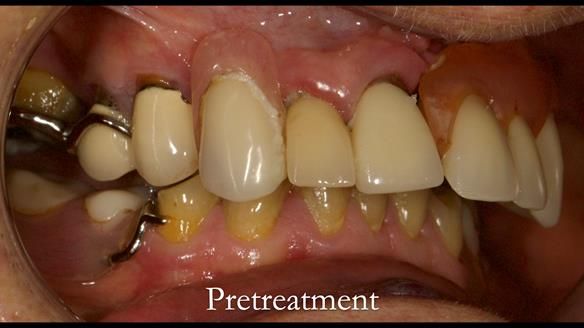

Aesthetically and functionally poor RPDs were replaced for Eileen, a 74 year old woman.

Referred to me by her general dental practitioner specifically for replacement RPDs.

Dental concerns

“Top denture loose making conversation difficult at times. Also, appearance isn’t good. Teeth uneven”

Diagnoses

- Missing teeth in the upper and lower jaws

- Upper and lower metal based RPDs, poorly fitting, worn occlusal surface, reverse curve aesthetics, lacking support

- Poor dental appearance with reverse incisal curve

- The upper right central and lateral incisors with post crowns. Healthy and functionally secure but with poor appearance, contributing to the reverse curve.

- Moderate to heavily restored dentition with deep overbite (Class 2 div II)

- Yellowish lower front teeth with small amount of wear.

- The lower right canine (LR3) is worn with MOD cavity.